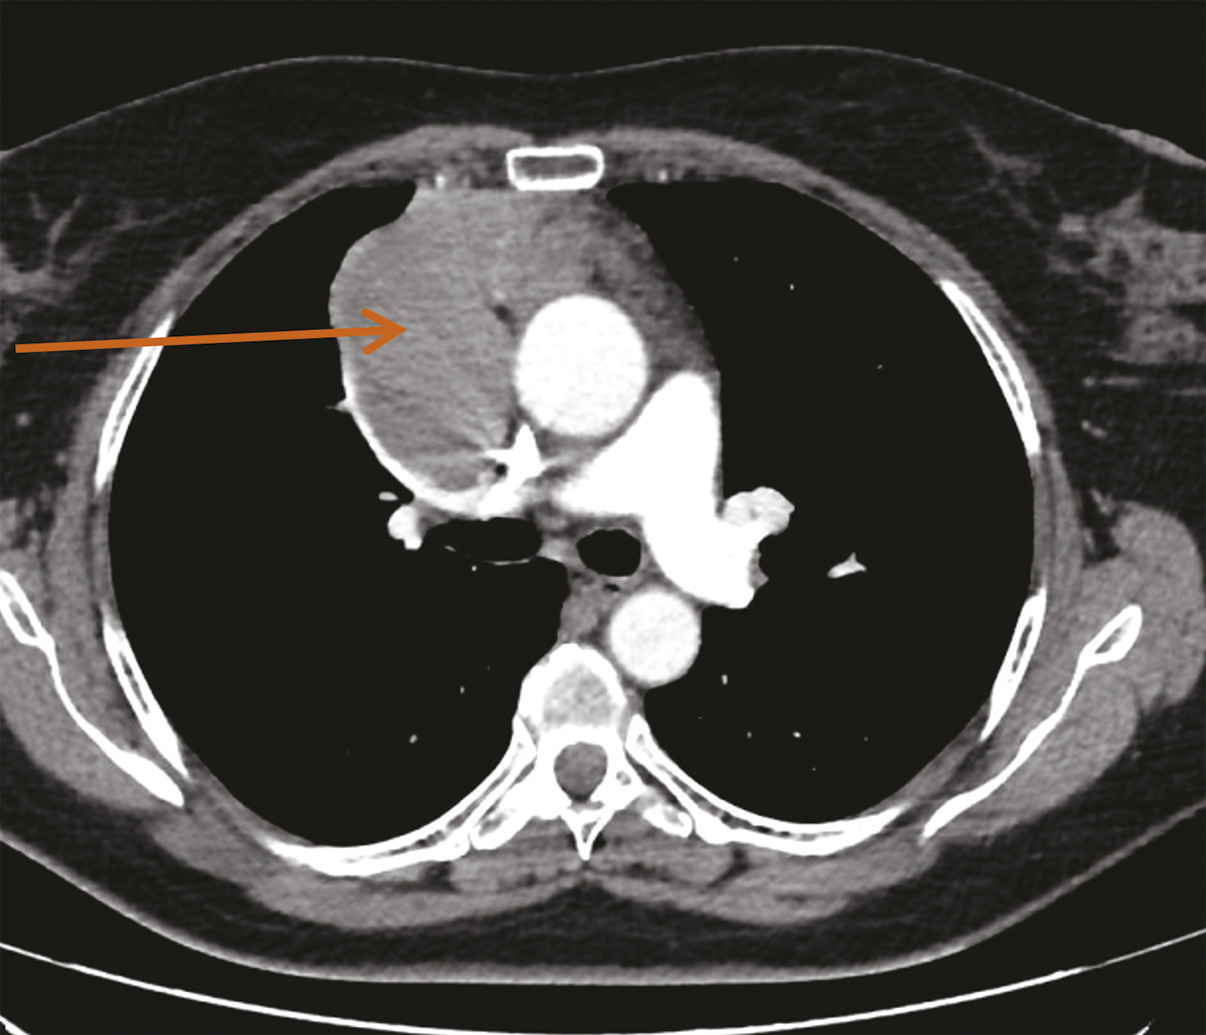

Une imagerie par résonance magnétique (IRM) du crâne réalisée 15 jours après le début des symptômes n’a pas montré d’anomalie. Toutefois, leur persistance et leur aggravation ont fait demander à son médecin traitant un dosage des anticorps antirécepteurs à l’acétylcholine, qui s’est révélé positif, conduisant au diagnostic de myasthénie. Des anticholinestérasiques ont alors été prescrits en première intention, permettant d’améliorer transitoirement les symptômes musculaires. Leur effet est de prolonger l’action de l’acétylcholine au niveau de la membrane post-synaptique par blocage réversible de l’acétylcholinestérase (deux médicaments sont disponibles : la pyridostigmine et l’ambénomium). Dans le cadre du bilan de cette myasthénie, une tomodensitométrie thoracique est pratiquée, qui met en évidence une masse médiastinale antérieure, volumineuse et polylobée évoquant une tumeur thymique (fig. 1).1

Le diagnostic différentiel d’un thymome est l’hyperplasie thymique, vraie ou lymphoïde. L’hyper­plasie thymique vraie, « rebond », doit être envisagée après un stress, des brûlures, l’administration d’une chimiothérapie, d’une radiothérapie, d’un traitement anti­hormonal, ou en cours de grossesse. Une hyperplasie lymphoïde thymique est fréquemment observée chez les patients atteints de vas­cularite, de connectivite, d’hyperthyroïdie ou de myasthénie. Sur la tomodensitométrie, l’hyperplasie thymique est une lésion médiastinale antérieure triangulaire, hétérogène, de densité mixte graisseuse. L’IRM, utilisant des séquences en contraste de phase (shift chimique/séquences Dixon), peut permettre une meilleure identification de cette infiltration graisseuse typique non tumorale : on observe alors une chute du signal en contraste de phase. La tomographie par émission de positons au 18-fluorodésoxyglucose n’est pas utile pour ce diag­nostic différentiel, mais peut être réalisée pour caractériser une lésion métastatique ou récidivante.

La première étape face à une lésion médiastinale suspecte de tumeur épithéliale thymique consiste en l’établissement du diagnostic différentiel avec les autres tumeurs du médiastin antérieur et les lésions thymiques non malignes. La tomodensitométrie thoracique est l’examen clé dans ce contexte. La nécessité d’une biopsie préthérapeutique dépend du doute diagnostique, et en outre de la résécabilité de la tumeur.